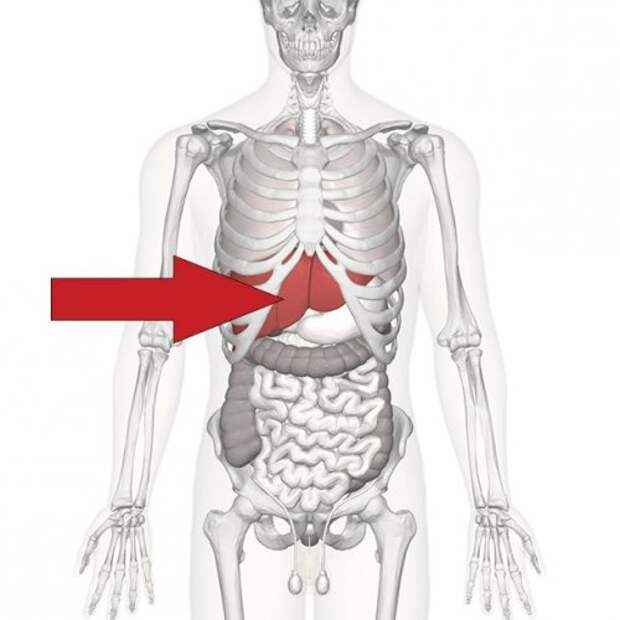

9. Печень – самый крупный внутренний орган, и он выполняет свыше 500 различных функций, включая борьбу с инфекциями и нейтрализацию токсинов.

9. Печень – самый крупный внутренний орган, и он выполняет свыше 500 различных функций, включая борьбу с инфекциями и нейтрализацию токсинов.